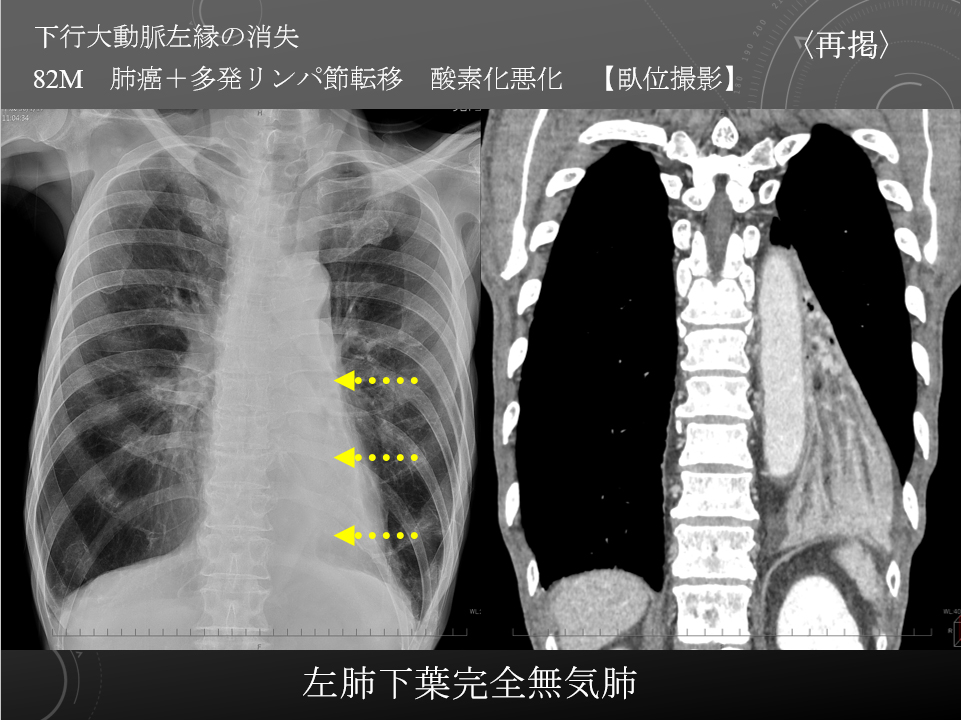

82M COPD 肺炎 酸素化悪化

原発性肺がん 多発リンパ節転移 左下葉完全無気肺 誤嚥性肺炎